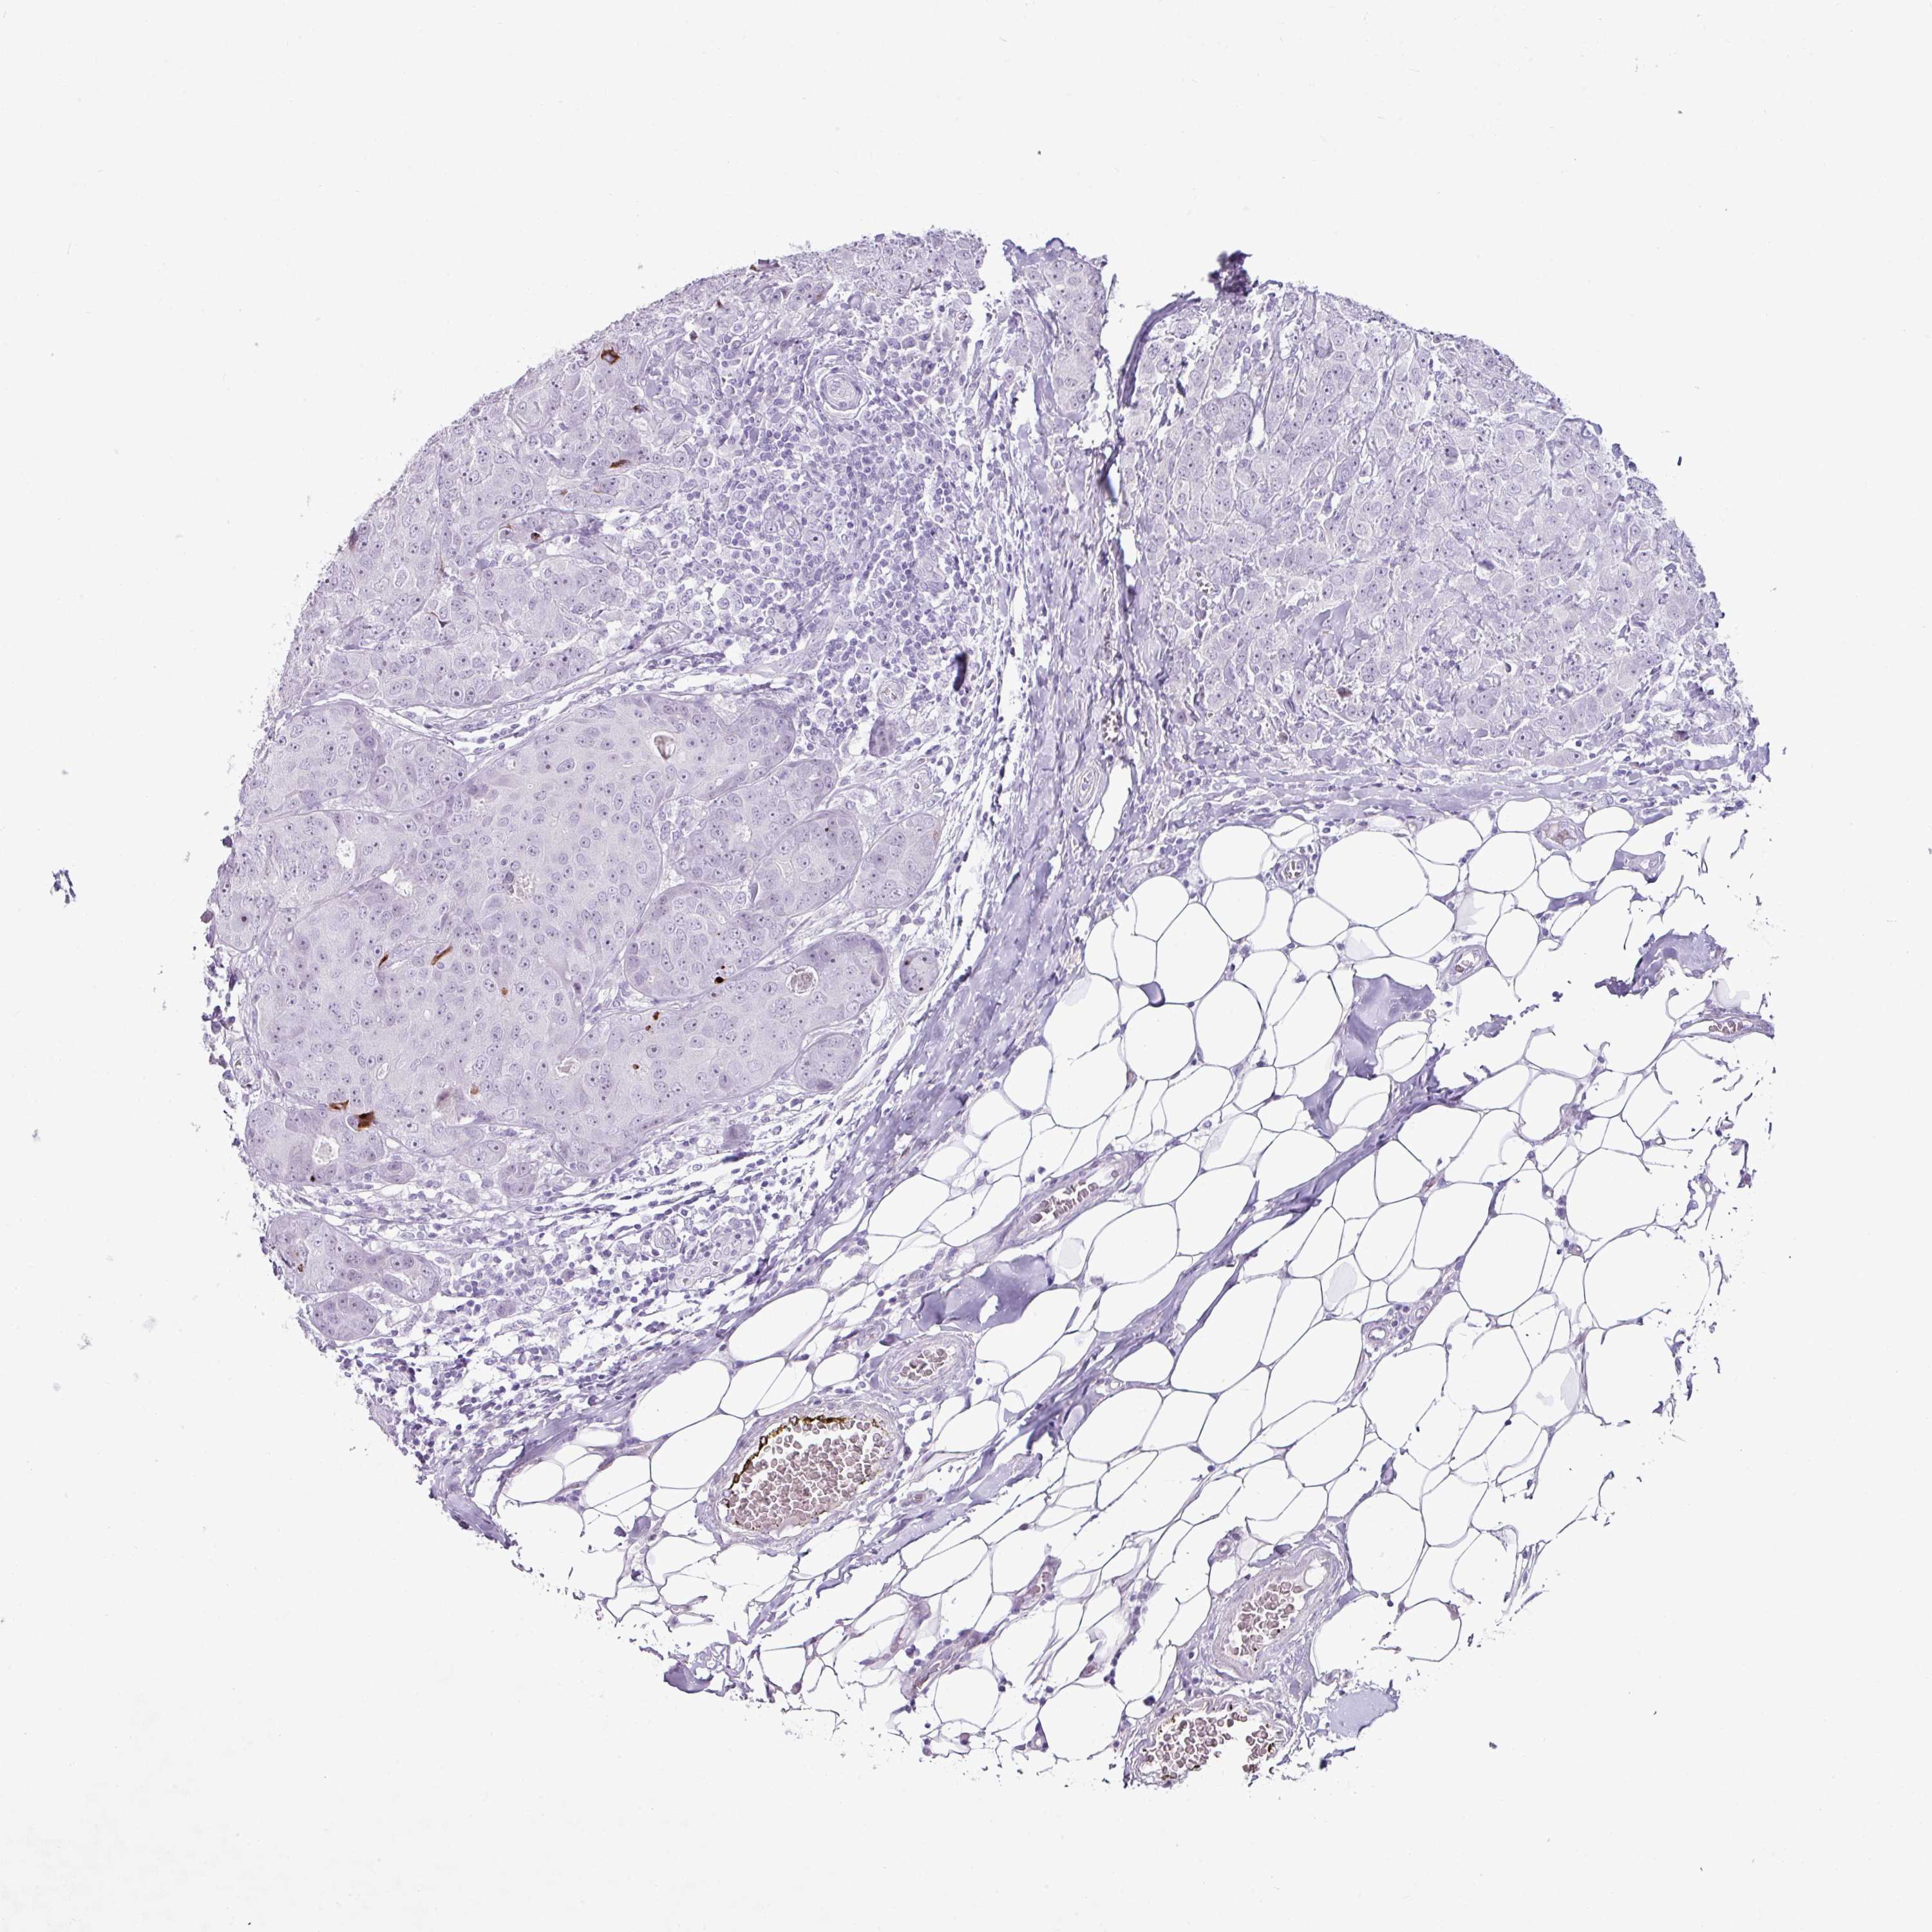

CANCER BREAST CANCER Show tissue menu

BRCA TCGA BRCA VALIDATION PROTEIN EXPRESSION